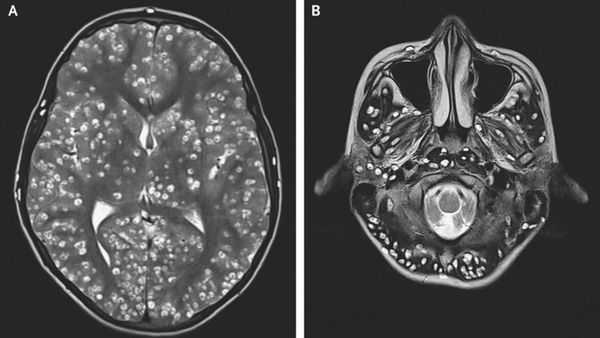

Цистицеркоз. Может быть осложнением тениоза, а может быть отдельным заболеванием. В основном симптоматика проявляется при поражении центральной нервной системы (ЦНС) — головного и спинного мозга и глаз. В зависимости от локализации возникают головные боли различной интенсивности, рвота, эпилептические припадки, нарушения речи, расстройства личности, бред и галлюцинации, деменция. При поражении глаз могут наблюдаться воспалительно-дистрофические процессы в различных отделах глаз — рецидивирующие конъюнктивиты, увеиты, отслоение сетчатки, атрофия глазного яблока, что может привести к слепоте. При поражении сердца могут возникать нарушения ритма. При поражении мышц и подкожной клетчатки иногда может наблюдаться некоторая болезненность при ощупывании и приподнятость этого участка в виде подкожного плотного опухолевидного бугорка [1] [5] [5] [8] .

Компьютерная (КТ) и магнитно-резонансная томография (МРТ), ультразвуковое исследование (УЗИ), прямая офтальмоскопия — применяются для выявления цистицеркоза. КТ лучше выявляет кальцификаты цистицерков (особенно небольшие). МРТ больше подходит для обнаружения цистицерков в некоторых трудновизуализируемых местах мозга, также МРТ указывает на местные окружающие изменения (отёк) и возможную гибель паразита.